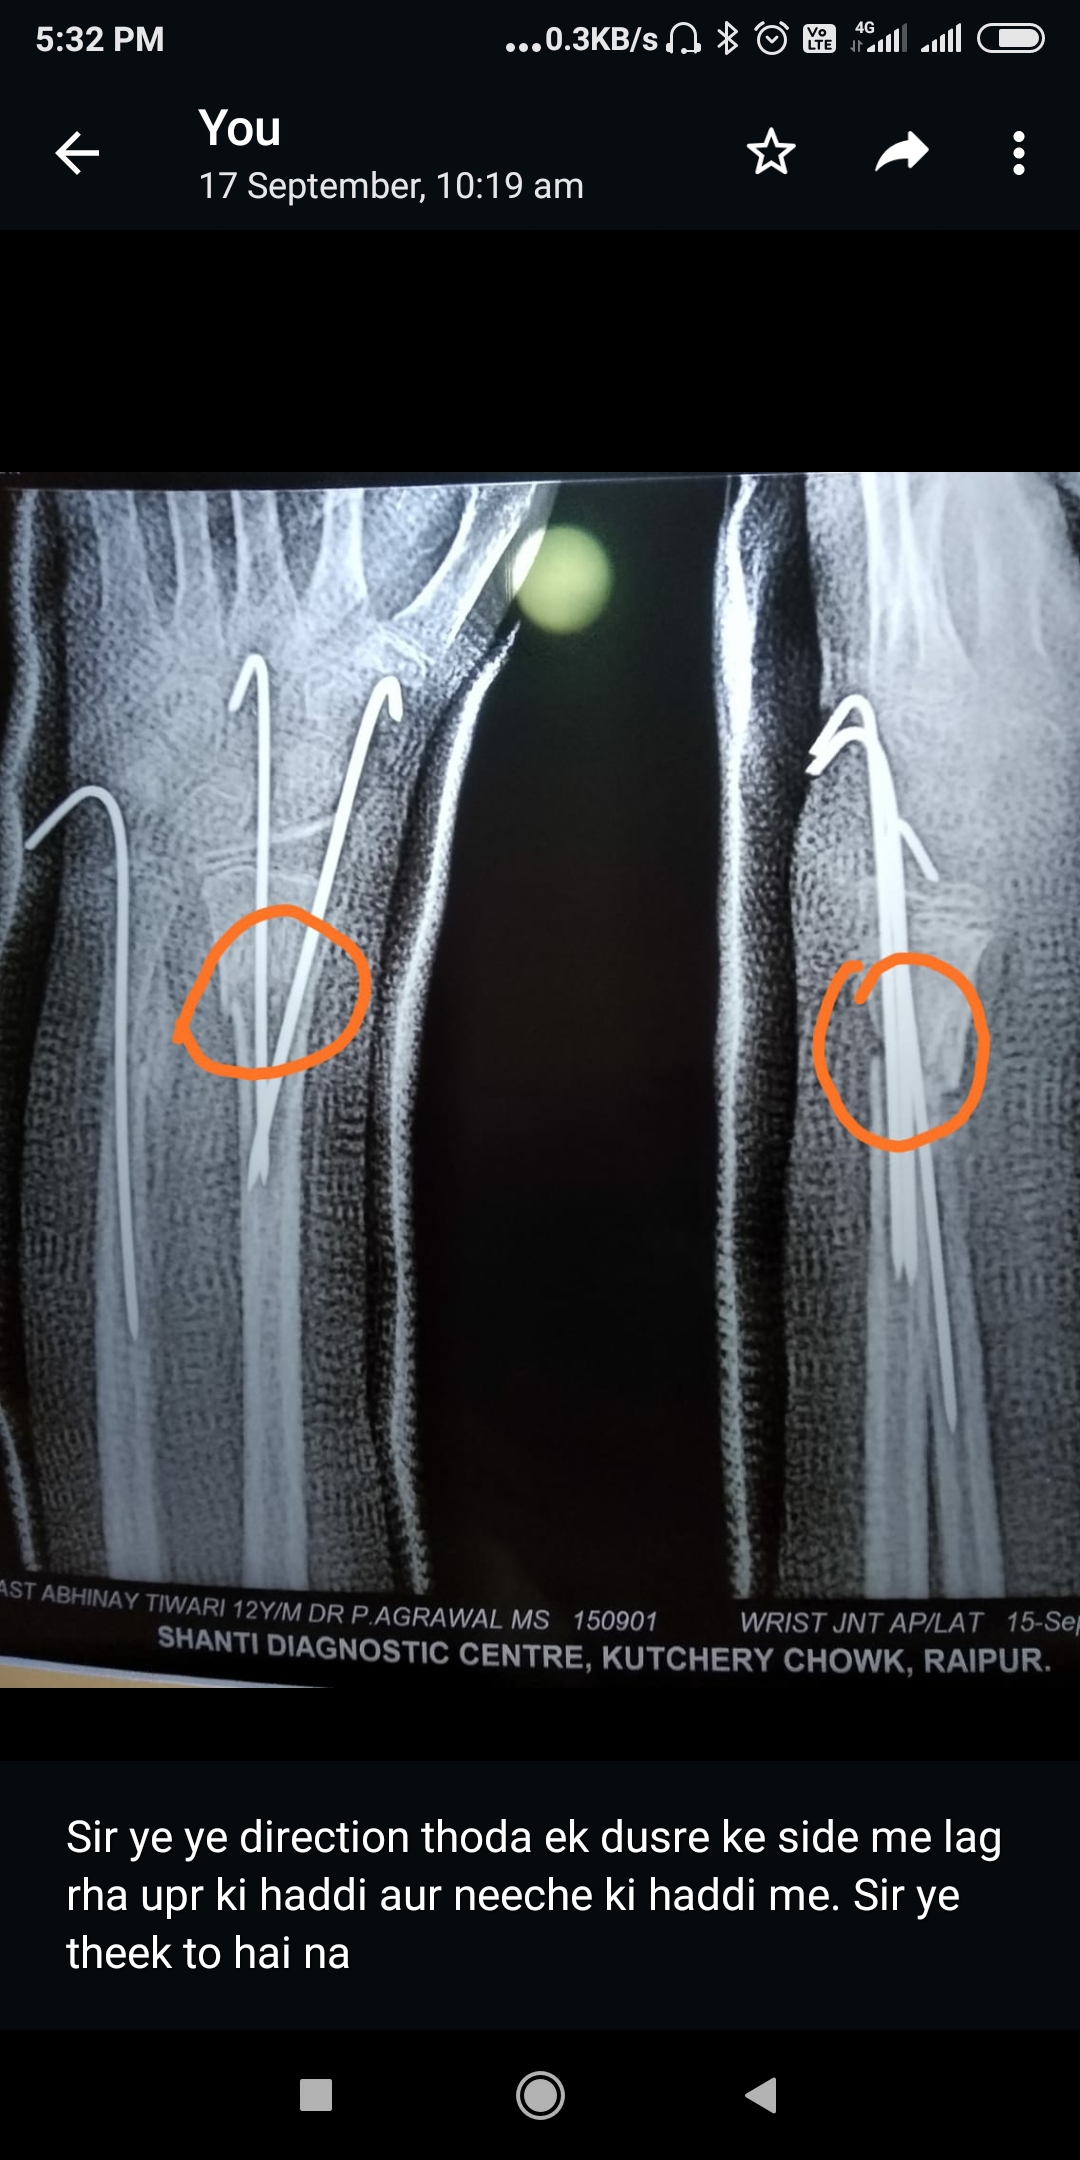

My 12 year old boy left hand wrist got fracture Redias and Ulna both on 5/8/2022 and dr operate it on 6/8/2022 with k wire. Now plaster and K wire remove on 15/9/22, Now I very worried to see Xray that it will it be come in perfect line and how muchh time it will take,